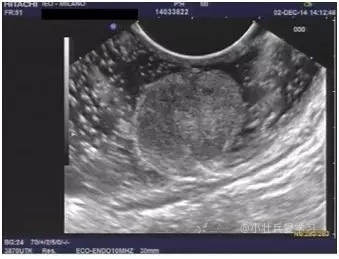

诊断直肠神经内分泌瘤,需要做超声内镜么?

答:直径超过1cm的直肠神经内分泌瘤需要超声内镜检查明确侵犯深度和排除肠周淋巴结转移,1cm以内的可以不做。